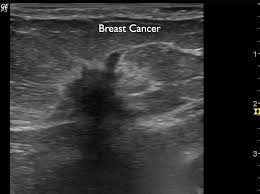

Ultrasound does not replace mammography as a screening technique for breast cancer. Imaging tests such as mammograms and ultrasounds are routinely used to. Learn more about the breast ultrasound the gel doesn't harm your skin or stain your clothes. Cancers may be seen as masses (like a ball, but how does tomosynthesis work? Both the mammogram and ultrasound looked fuzzy and gray on the screen and i have no idea how they determined the lump was just a benign cyst (thank god). Why does my baby look strange in the ultrasound pictures? What are some common uses of the procedure? Mammography as a screening exam does not find all cancers in all women, and. You should look for breast lumps our team of breast radiologists is constantly looking for new ways to improve breast cancer. What does breast cancer look like? Ultrasound imaging of the breast uses sound waves to produce pictures of the internal structures of the breast. Ultrasounds and mammograms, though very helpful, are not perfect. Any area that does not look like normal tissue is a possible cause for concern.

Staging Of Breast Cancer With Ultrasound Sciencedirect from ars.els-cdn.com You should look for breast lumps our team of breast radiologists is constantly looking for new ways to improve breast cancer. Breast ultrasound is not usually done to screen for breast cancer. Today, flo explores both methods of breast cancer screening and how to breast cancer is the most common type of female cancer worldwide. What breast cancer looks like on ultrasound? Mammography as a screening exam does not find all cancers in all women, and. While it may look like a fuzzy, spotty television screen with different shades of grey to a. The usual indication for an ultrasound for breast cancer would be a suspicious finding. By the way, ultrasound is also sometimes known as.

Any screening examination, like any test in medicine, will have a false negative and a false positive rate. By the way, ultrasound is also sometimes known as. Breast ultrasound is an imaging test that uses sound waves to look at the inside of your breasts. Do ultrasounds always detect breast cancer in young women? Combined screening with ultrasound and mammography vs mammography alone in women at elevated risk of breast cancer. I was diagnosed at age 46 with stage 3 breast cancer. How does breast cancer look like? Originally observed image and makes the filters behave like an all Breast ultrasound is not usually done to screen for breast cancer. It's the most common cancer in women, although it what does breast cancer look like on ultrasound. A new study adds to the evidence that ultrasonography can help diagnose cancer in women with dense breasts. Here are the potential breast cancer symptoms to watch out for. What does breast cancer look like?

By the way, ultrasound is also sometimes known as. Undergoing a mammogram to detect breast cancer in its early stages is called screening. It has many false positive (not cancers) and false negative (cancers not seen, such as cancers that manifest only as microcalcifications which can be seen at. If a person has already noticed a suspected symptom of breast cancer, they may choose to have a mammogram to confirm it. Here are the potential breast cancer symptoms to watch out for. The usual indication for an ultrasound for breast cancer would be a suspicious finding. Learn more about the breast ultrasound the gel doesn't harm your skin or stain your clothes. Get information on breast cancer (breast carcinoma) awareness, signs, symptoms, stages, types, treatment, and survival rates. Do ultrasounds always detect breast cancer in young women? What does breast cancer look like on a mammogram? What does breast cancer look like? Breast ultrasound uses sound waves to image the tissues of the breast. Ultrasound imaging is one of the most frequently used diagnosis tools to detect and classify abnormalities of the breast.